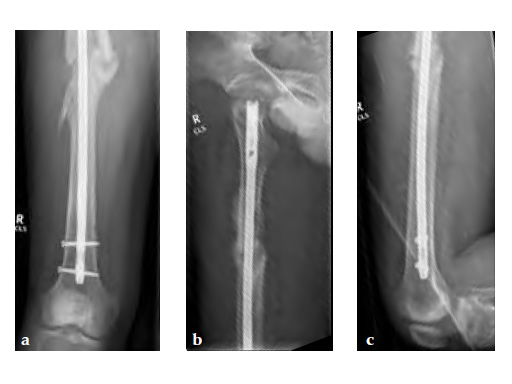

Note despite the increased in curvature compared to other nails in the market, there is still noticeable malreduction at the fracture site (see Fig 6a-b).

Patient was allowed and achieved immediate weight bearing and in 6 weeks callus is seen at the fracture site (see Fig 7a-b).